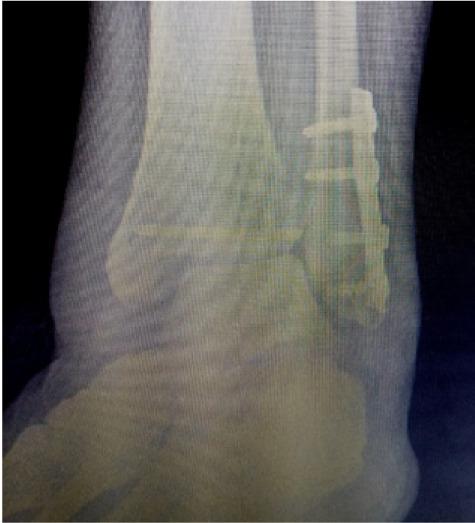

We report a case of 49- year old patient with a Maisonneuve fracture. The first surgery has failed with three-cortical screw rupture.  The second surgery was based on the implantation of quadricortical screw, zip tight and fibula elongation with autograph. The results were excellent despite the patient having contracted Covid-19 virus during rehabilitation.

报告一例 49 岁 Maisonneuve 骨折患者。第一次手术失败,三皮质螺钉断裂。第二次手术采用 quadricortical 螺钉、Zip 固定和自体腓骨延长。尽管患者在康复期间感染了新冠病毒,但结果仍为优。